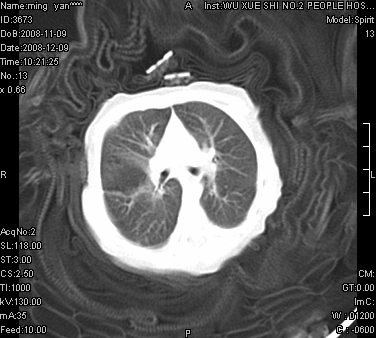

女.30天.咳嗽.喘3天.系三胞胎

考虑右肺下叶先天性肺囊肿,不除外合并右中叶肺发育不全

伴双肺感染

考虑右肺下叶先天性多发性肺囊肿可能。

考虑右肺下叶肺囊肿伴感染,右中叶节段实变或发育不全

这是一个先天性囊性腺瘤样畸形(congenital cystic adenomatid malformation,ccam),属于先天性肺发育异常,最近国外文献重新命名为先天性肺气道畸形(congenital pulmonary airway malformation,cpam),根据发生部位和畸形组织与气管、支气管的关系分成五型。本病以1岁以下婴儿多见,男性多于女性。病因为终末呼吸单元的异常增殖,形成多囊状结构。国内根据影响和病理表现分三型:ⅰ型为单个或多个大囊肿,直径大于2cm;ⅱ型为多个小囊肿,直径小于2cm;ⅲ型为大的非囊肿性病变,但显微镜下观察可见肿块由多发小囊组成(直径小于2mm)。本病可发生于肺内任何一部分,单侧肺占95%,中叶病变相对较少。